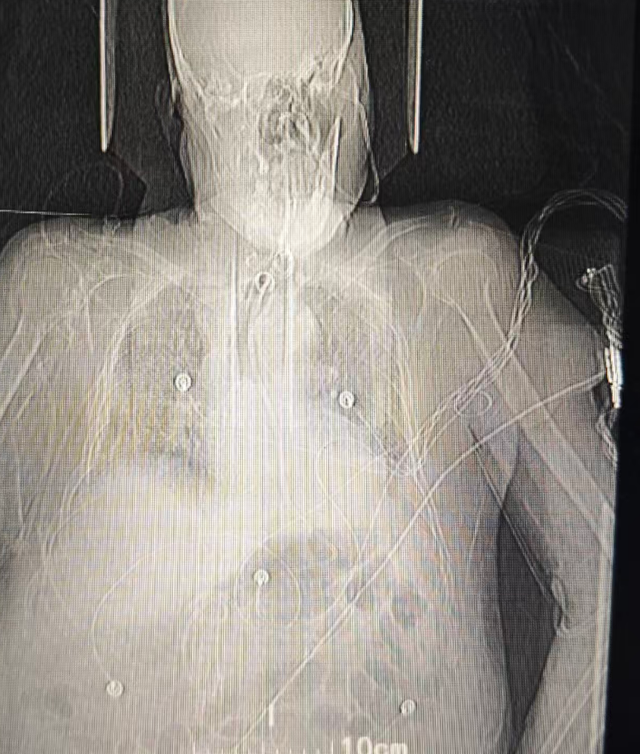

(置入鼻肠管X线影像)

为解决这一难题,重症康复科医护团队为管大爷进行了鼻肠管置管。这根管子更细、更软,顺着鼻腔经过胃,一直放置到十二指肠或空肠(小肠的中上段)。

经过一段时间的鼻肠管营养支持,管大爷的营养状况得到了改善,胃肠功能逐渐恢复,为后续的治疗争取了宝贵的时间和体力。对于长期住院、胃功能不佳的重症患者来说,鼻肠管不仅是营养的“生命线”,更是保障治疗安全、促进康复的重要工具。